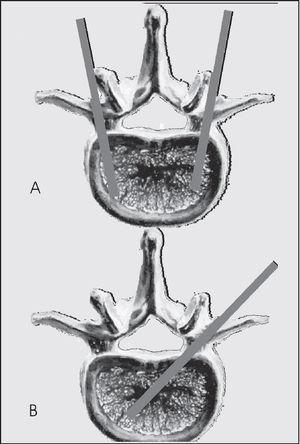

En estos pacientes se realiza un estudio mediante resonancia magnética (RM), empleando secuencias sagitales potenciadas en T1 y secuencias T2 con supresión grasa (STIR).

En las secuencias potenciadas en T1, la fractura vertebral reciente se manifiesta con una disminución de la señal de resonancia. En las secuencias potenciadas en T2 con supresión grasa o STIR, la manifestación es una hiperseñal, fácilmente identificable por la supresión grasa; estos cambios de señal traducen la presencia de edema y se correlacionan con un proceso agudo, susceptible de ser tratado mediante vertebroplastia (fig. 1).

Figura 1. A: resonancia magnética sagital de columna con secuencia espín eco potenciada en T1: las fracturas agudas en L3, L2, T12 que presentan disminución de la intensidad de señal, fracturas vertebrales consolidadas, sin edema, en territorio dorsal medio. B: resonancia magnética sagital con secuencia espín eco potenciada en T2 con supresión grasa, hiperseñal en las vértebras con fractura reciente.